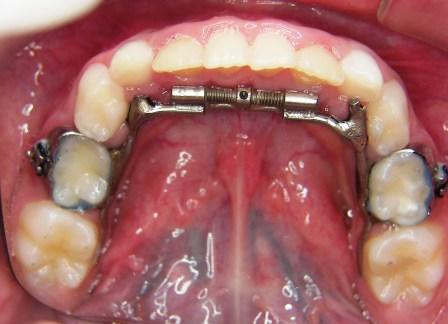

Crossbite - before and after: